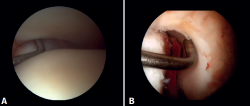

Evaluación artroscópica de la sindesmosis

Evaluación artroscópica del ligamento deltoideo

Existen múltiples métodos para evaluar la inestabilidad del complejo medial; mediante los portales anteriores del tobillo es posible valorar la estabilidad del ligamento deltoideo en su plano principal de acción, correspondiente al plano coronal. Chun et al.(20) describió inestabilidad cuando es posible introducir un palpador artroscópico en el espacio medial tibioastragalino (Figura 6B). Vega et al.(21) describió que, en la mayoría de las lesiones, la porción más anterior del ligamento deltoideo está desprendida del maléolo medial, mientras que sus inserciones proximales permanecen íntegras. En esta situación se puede introducir el palpador artroscópico entre la pared medial del maléolo interno y las fibras profundas del deltoideo.

Figura 6. Maniobras para evidenciar inestabilidad ligamentosa. A: lesión de la sindesmosis que permite la introducción del palpador en la tibioperonea distal; B: lesión del deltoideo que permite la introducción del palpador en el espacio medial tibioastragalino.